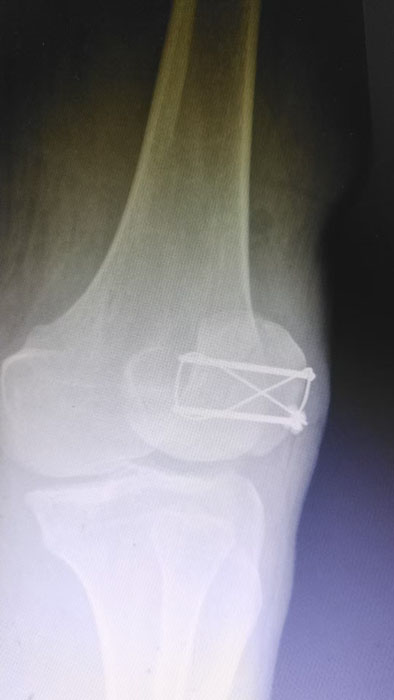

精湛施術 安全有序,守護患者健康

手術現場,徐三軍主任憑借多年積累的臨床經驗和嫻熟的手術技巧,精準完成骨折復位、鋼板內固定、傷口縫合等一系列關鍵操作,動作規范流暢、精準高效,最大限度減少手術創傷。該院外科醫護團隊全程密切配合、協同發力,嚴格按照手術規范操作,全程嚴密監測患者心率、血壓等生命體征,及時應對術中各類突發情況,全力保障手術安全。此次手術全程順利,術中出血量少,患者生命體征始終平穩,術后患者順利安返病房,為后續康復治療奠定了堅實基礎。